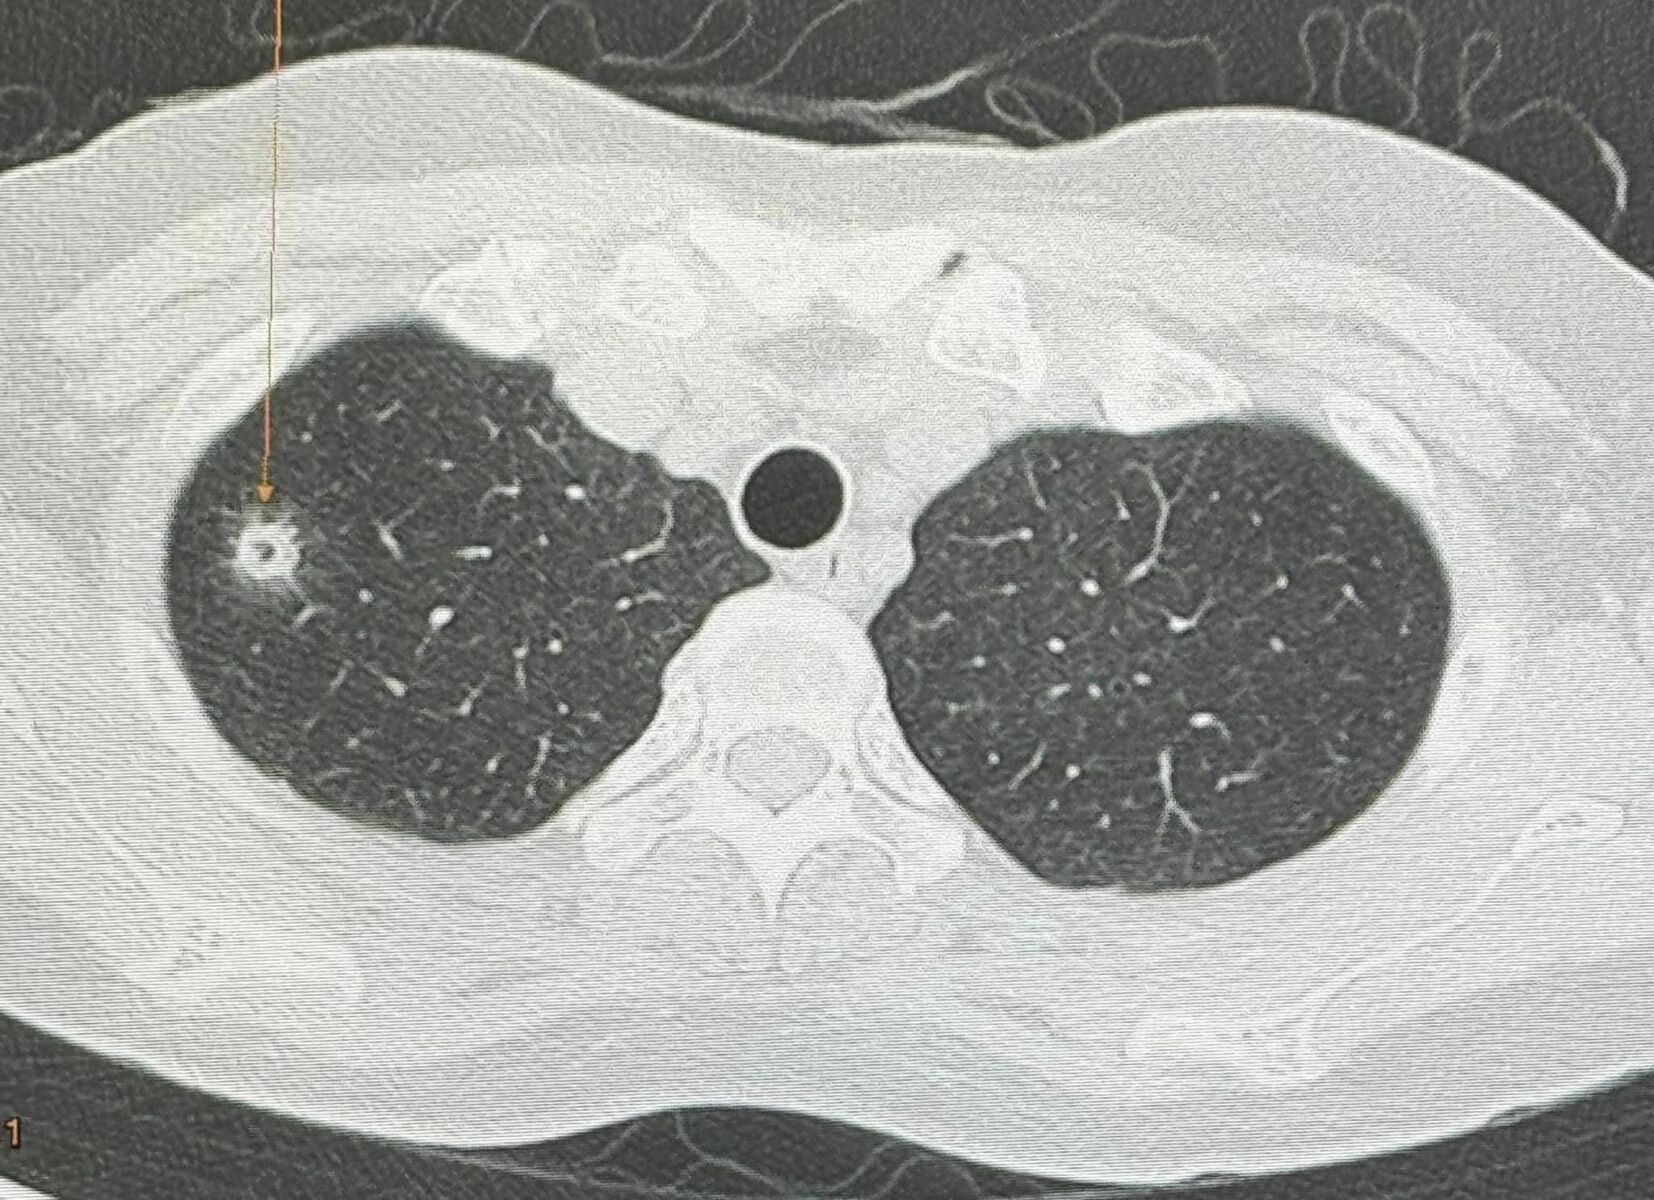

During a routine annual check-up on May 12, an X-ray revealed a new small mass in the upper lobe of her right lung. A previous X-ray from the year before was normal. A CT scan showed the mass measured 0.9 by 0.9 by 1.7 centimetres, with a cavity inside.

The pathology report identified the mass as cryptococcal pneumonia, caused by the fungus Cryptococcus Neoformans. Four days post-surgery, a blood test for cryptococcal antigen came back positive with a titer of 1:8. The patient began treatment with the antifungal medication fluconazole. Seeking further advice, she consulted with her doctors on the next steps.